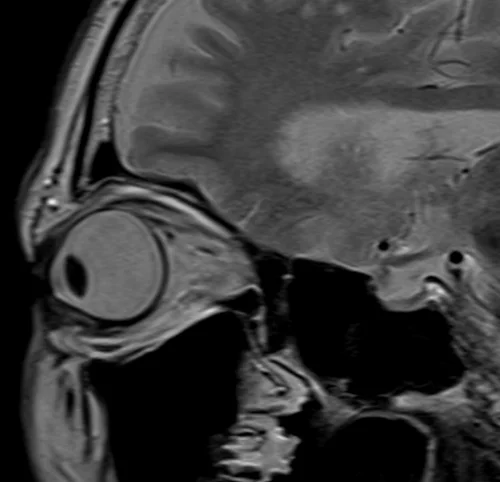

MRI Orbits T2 sagittal oblique images